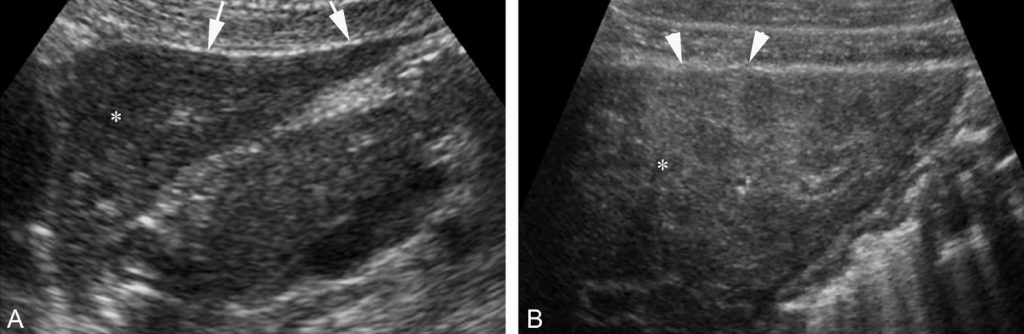

La fibrose et les nodules de régénération qui composent la cirrhose sont visibles sous forme d’une hétérogénéité du parenchyme et d’une irrégularité des contours hépatiques qui ont souvent un aspect bosselé (figure 5.2).

Fig. 5.2 Aspect échographique comparatif d’un foie sain (A) et d’un foie de cirrhose (B) (coupe sagittale du foie gauche).

Le foie sain présente un parenchyme d’aspect homogène (∗) et des contours lisses (flèches). Le foie cirrhotique est d’échostructure grossière et hétérogène (∗). La surface du foie est bosselée (têtes de flèches).

Source : CERF, CNEBMN, 2022.